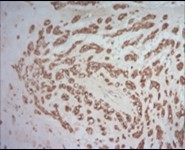

Multinodular tumour architecture is constituted by miniature, uniform, elliptical or spindle-shaped cells with scanty, eosinophilic, finely vacuolated cytoplasm and miniature, regular or hyperchromatic nuclei. Myxoid tumour matrix is envelops neoplastic cells configuring cords and strands. Nuclear pleomorphism is absent. Tiny foci of necrosis with focal chondroid differentiation may ensue6. Meningo-endothelial cells, physaliferous cells, rhabdoid cells, ductal differentiation and anaplastic cellular dedifferentiation is usually absent. Myoepithelial carcinoma displays nuclear atypia, elevated mitotic rate and extensive foci of tumour necrosis5. Figure 1, Figure 2, Figure 3, Figure 4, Figure 5, Figure 6, Figure 7, Figure 8.

Figure 7.Parachordoma depicting immune reactivity to S100 protein 16.

Parachordoma is immune reactive to cytokeratin CAM 5.2 and glial fibrillary acidic protein (50%). A subset of tumour cells are immune reactive to CD99 and smooth muscle actin (SMA). Stroma is intensely highlighted with an alcian blue stain wherein staining intensity is reduced following hyaluronidase digestion. Tumour cells are immune reactive to epithelial membrane antigen (EMA), CK8/18, S100 protein, calponin (50%), vimentin, type IV collagen and CD117 6.